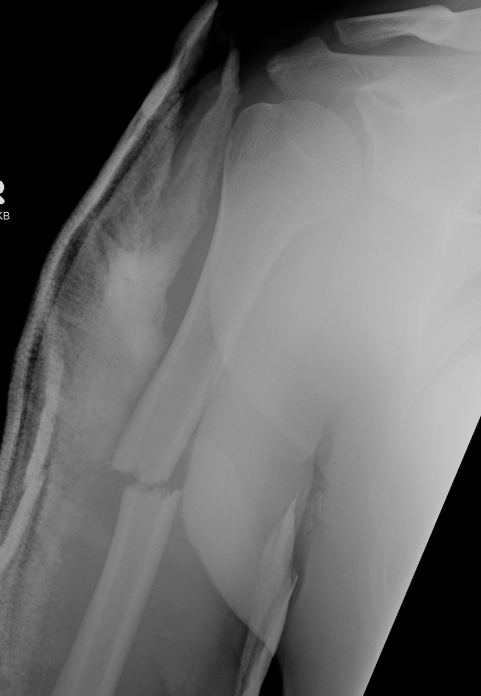

Humeral Shaft Fracture

Non operative Management

Indications

< 20o sagittal

< 30o coronal

< 3 cm of shortening

Xray Assessment

A: Alignment

B: Bony

C: Canal

D: Disc

S: Soft tissues